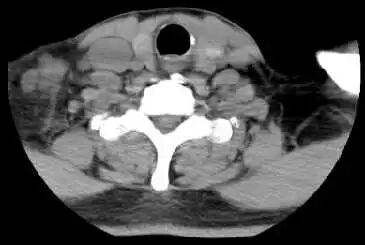

2022-09-20  颈部+胸部CT增强示:右锁骨上下窝见多发肿大淋巴结影,较大者约22×21mm;右肺上叶前段实性结节,大小约为17×8mm ;纵隔内见肿大淋巴结影,大小约11×23mm。

影像学检查图像(基线)